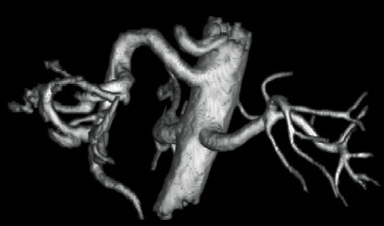

RADAR’ın TOF MRA ve GrE T2*WI’deki etkileri

RADAR, yüksek hassasiyetli sinyal düzeltme teknolojisi kullanılarak GrE sekanslarına uygulanmıştır. Bu, rutin baş incelemelerinde gerekli tüm sekanslar için RADAR’ın kombine kullanımını mümkün kılmıştır.